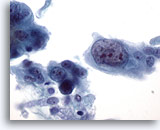

Figure 76

Sputum

Orangeophilic cells with hyperchromatic nuclei are suspicious for squamous cell carcinoma. 60x

Sputum

Orangeophilic cells with hyperchromatic nuclei are suspicious for squamous cell carcinoma. 60x